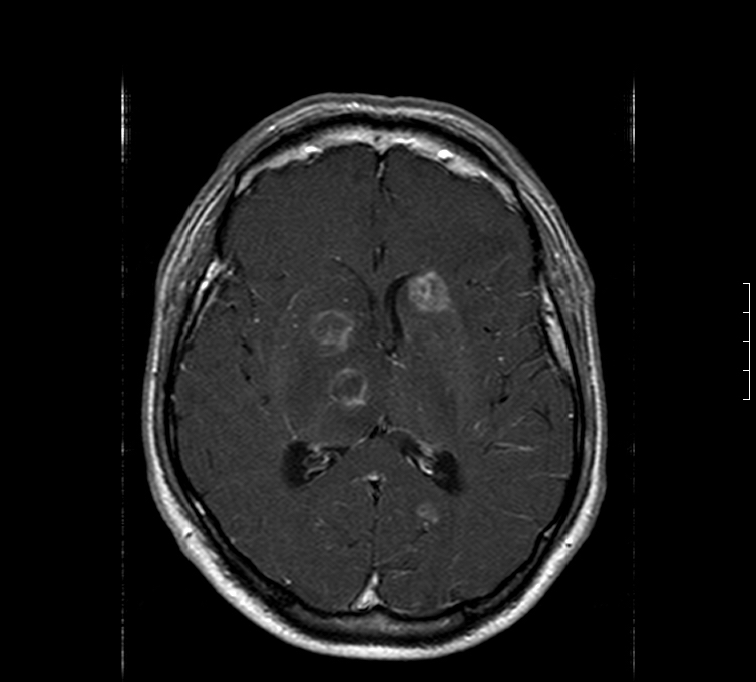

Ring-enhancing abscesses in brain

Toxoplasmosis

Toxoplasmosis or primary CNS lymphoma

(multiple ring-enhancing lesions in AIDS patient brain)